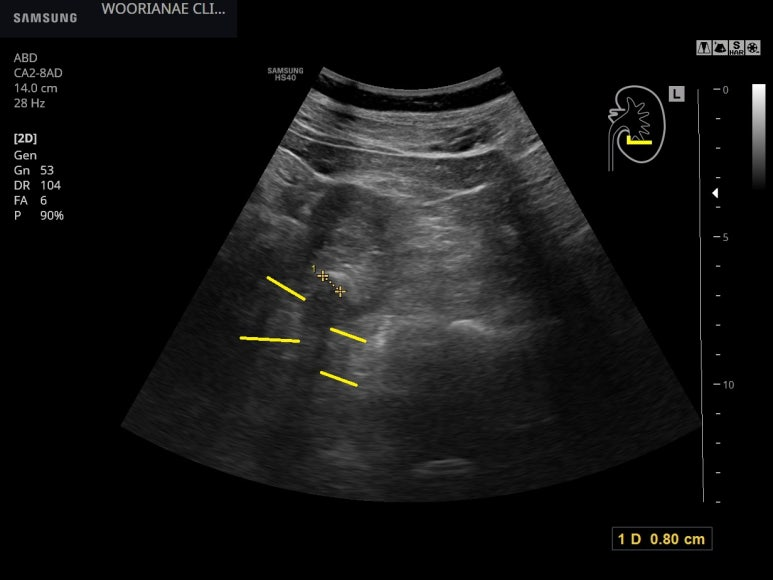

점심이후 5시간이 지났으니 공복으로 봐야할지.. 식후로 봐야할지 애매하나

담낭은 압력이 올라간, 팽대한 느낌

간내 담도 확장은 없었으며, 담낭벽의 비후도 없다.

여러 각도에서 담낭목을 관찰하는데 뚜렷한 담석은 발견되지 않았다.

수년간 무증상으로는 거의 관찰하지 못했는데... 신장내 결석이 관찰됨

후방감쇄가 동반되어 뚜렷하다.